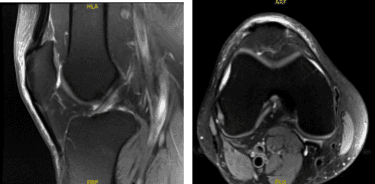

The patient presented MRI results that showed mild to moderate insertional quadriceps and proximal patellar tendinosis. There is prominent spurring along the inferior pole of the patella without a separate ossific fragment or surrounding bone marrow edema indicative of previous traction injury.

No meniscal tear or ligament injury. Cartilage is preserved. For the right knee, the X Ray results have shown Shallow undersurface tear at the posterior horn/body junction of the medial meniscus and undersurface fraying of the posterior horn.

Mild quadriceps and patellar tendinosis without a tear. Mild prepatellar bursitis and moderate surrounding soft tissue edema. We discussed treatment with the patient. The patient had tried physical therapy in the past.

MRI-3T Left Knee non-contrast

MRI-3t Right Knee non-contrast